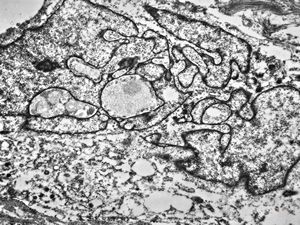

F,69y. | regenerating muscle cell

F,56y. | regenerating muscle cell